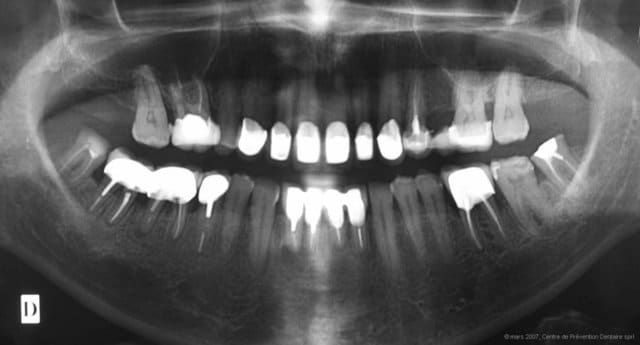

La pano qui ne sert à rien dans le diagnostic occlusal : c'est ici.

Occlusodontologie 06 bzlein - Eugenol